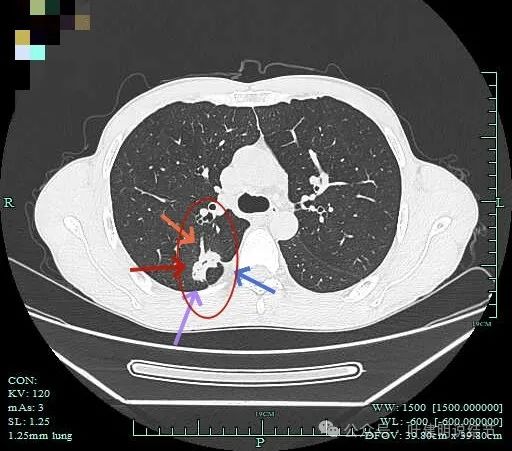

右上病灶1:

病灶出现,密度较高,不是圆形或类圆形,边缘略模糊。

病灶似乎有卫星灶,中间有小空泡征,边缘有晕。

感觉周围略糊,有晕的感觉。

上面层面密度较高。

似乎有毛刺征,但膨胀性不明显。

有部分边缘显毛糙。

点状高密度,有晕的感觉。

点状高密度结节。

点状高密度之外,蓝色箭头示周围有淡磨玻璃影。

风轻云淡磨成分明显且轮廓不清。中间的点状高密度显得不够致密,缺乏收缩力。

边缘区仍有淡磨形态的晕

此灶从连续层面上看,是自右上前侧斜行向左下后侧延伸的,整体病灶偏长条些,而且有晕、有淡磨成分,实性部分缺乏收缩力或膨胀性,更符合炎性病灶的恢复期或吸收不全的阶段。